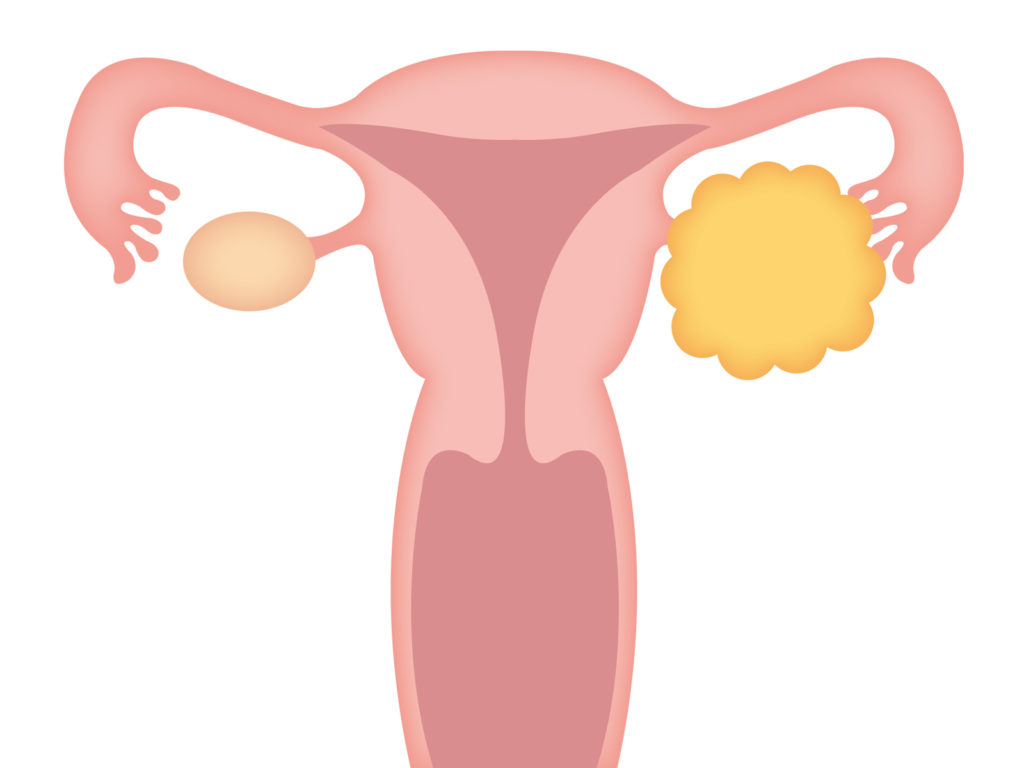

卵巣嚢腫、または卵巣嚢腫は、液体と空気で満たされた薄い膜で囲まれた泡のように見えます。骨盤領域の痛み、膨満感、腹部の重さ、月経の遅れ、または妊娠の困難を引き起こす可能性があります。

月経周期中、卵巣は通常、卵胞と呼ばれる嚢胞状の構造を形成し、ホルモンのエストロゲンとプロゲステロンを生成し、排卵するたびに卵子を放出します。正常な毎月の卵胞が成長を続ける場合、それは機能性嚢胞として知られます。

- 黄体嚢胞: 卵子が卵胞から放出された後に発生し、通常は少量の血液が含まれています。

- 子宮内膜腫– 子宮内膜細胞が子宮の外で増殖するときに発生します(子宮内膜症)。組織の一部が卵巣に付着して嚢胞を形成する場合があります。